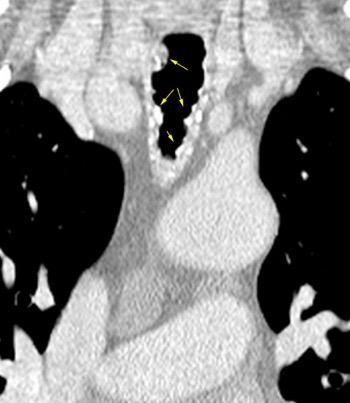

Traqueobroncomegalia de Mounier-Kuhn

Dilatación marcada de tráquea y grandes bronquios.

Traqueobroncomalacia 67% + Protrusión del tejido músculo-membranoso redundante entre los anillos cartilaginosos.(diverticulosis traqueal)

Infección respiratoria recurrente (88%)

Debilidad del aparato muco -ciliar Fumadores.

Schmitt P et al. Respiratory Conditions Associated with Tracheobronchomegaly (Mounier-Kuhn Syndrome): A Study of Seventeen Cases. Respiration 2016

Wegner F. CT of Mounier-Kuhn Disease. Radiology 2020